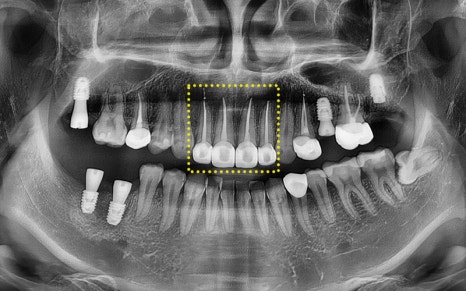

You can also check on the panoramic image

that the treatment was carried out successfully.

Currently, the implant is in a state where only the fixture,

which is the artificial root part,

has been placed,

and we plan to complete the prosthetic process

by later placing the crown (prosthesis).

In particular, treatment was carried out across a wide area,

including the upper front teeth and molars.